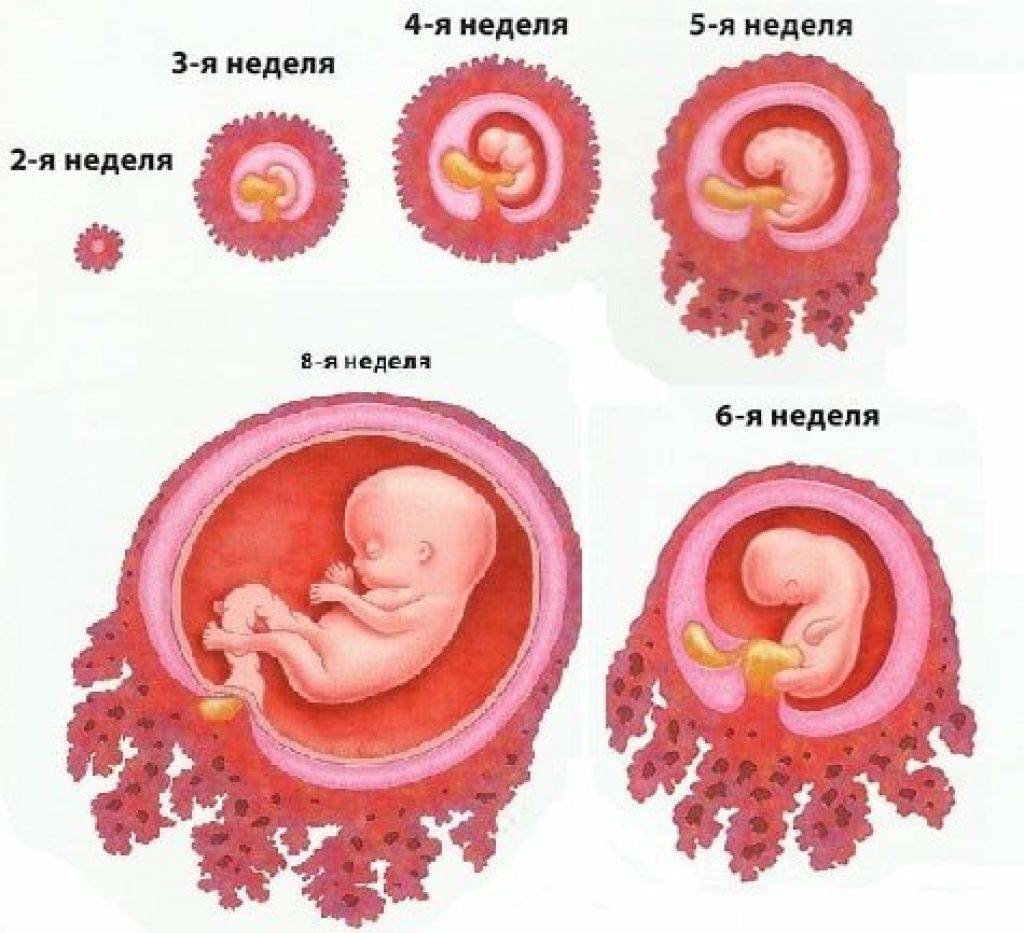

Развитие эмбриона: Что происходит на 3 неделе беременности

Раздел: Фотопанорама